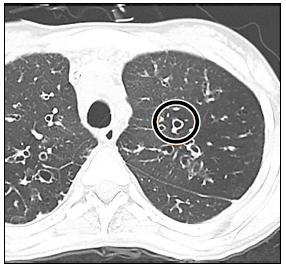

Observe o sinal encontrado em uma tomografia computadorizada:

Assinale a alternativa que apresenta

o sinal, associando-o a uma patologia causadora.

Sinal do crescente aéreo, comum na aspergilose.

Sinal do anel de sinete, que pode ser causado por um adenocarcinoma metastático, por exemplo.